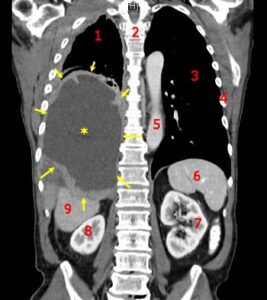

Photo credit: en.wikipedia.org via Google